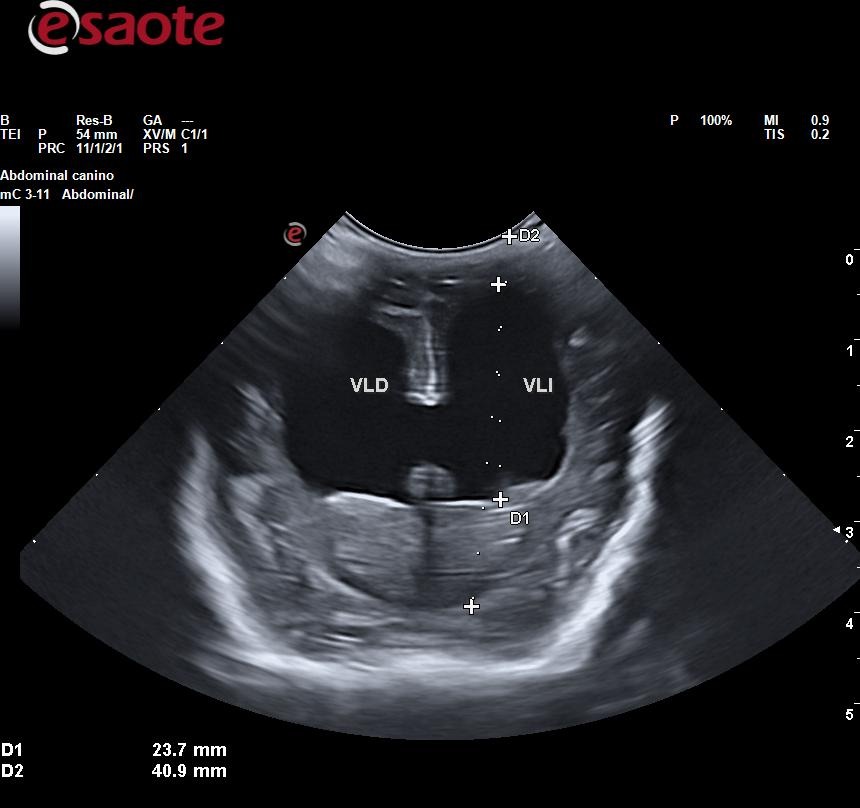

Sienna padece hidrocefalia, una condición muy delicada que pone en riesgo su vida. Fue vendida por un criador y, poco después, sus anteriores tutores nos la trajeron en medio de una crisis convulsiva muy grave. Además, como consecuencia de esas convulsiones, desarrolló una neumonía por aspiración severa que actualmente estamos tratando en la clínica donde trabajo.

Creemos sinceramente que esta pequeña tiene una oportunidad real de salir adelante. Sin embargo, para ello necesita pruebas especializadas, como una resonancia magnética, que solo pueden realizarse en un hospital de referencia con servicio de neurología. Estos estudios son costosos y exceden por completo lo que nosotros, como trabajadores, podemos asumir.